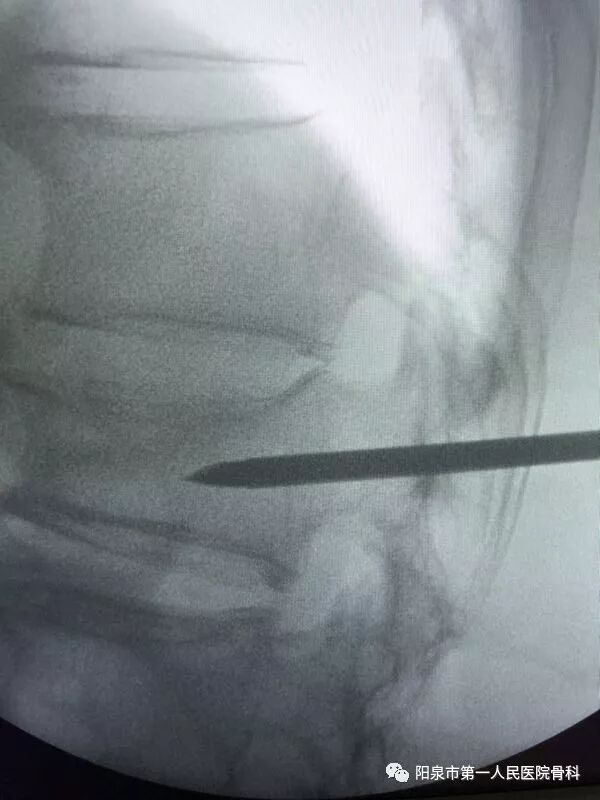

下面为在C臂机透视下观察到的穿刺操作过程,正侧位分别透视来确保正确的穿刺部位。图中黑色直杆为穿刺针。

椎体成型需要哪些器材椎体成形术概述_https://www.jmylbn.com_新闻资讯_第25张